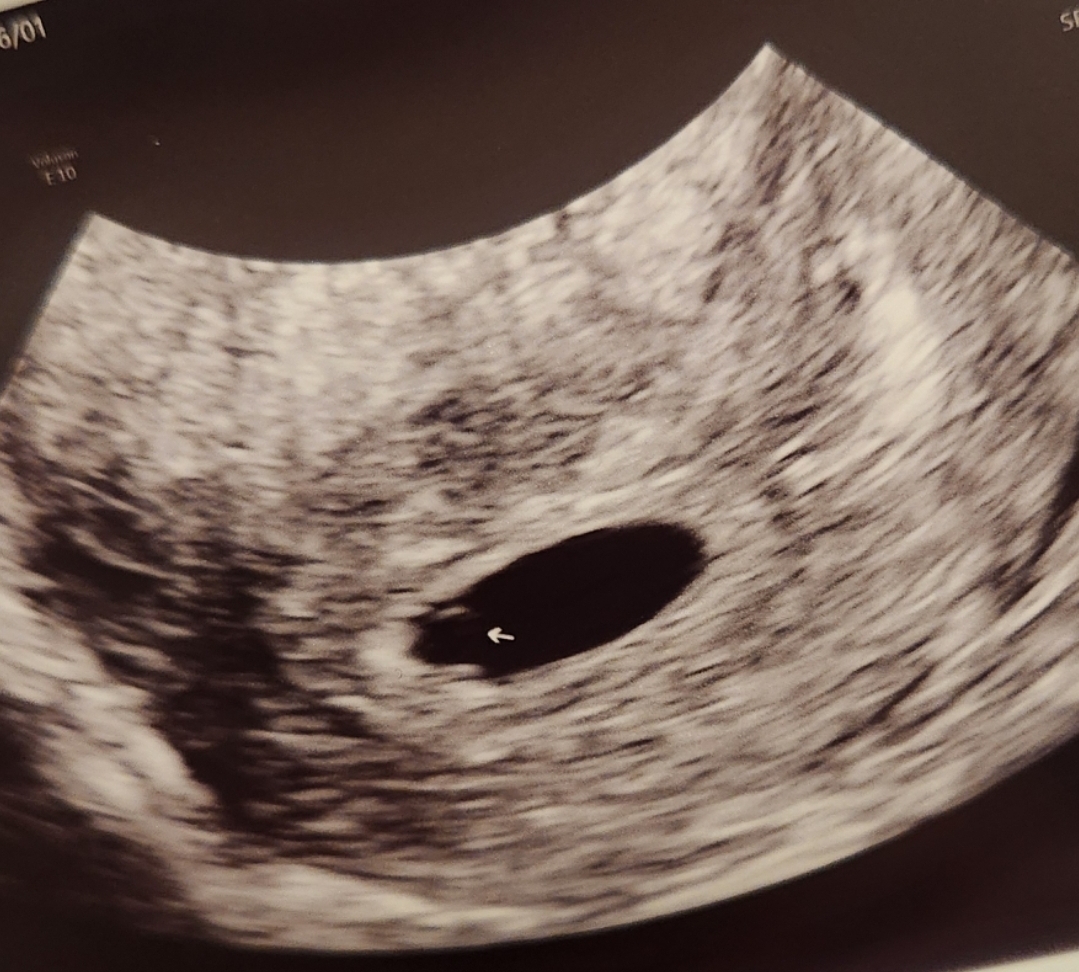

5주3일, 아기집1.6cm난황 보고왔어요

ㅎㅎㅎ아기도 봤으면 했는데 난황만 보고 와서 넘 아쉬워요. 흐흐.